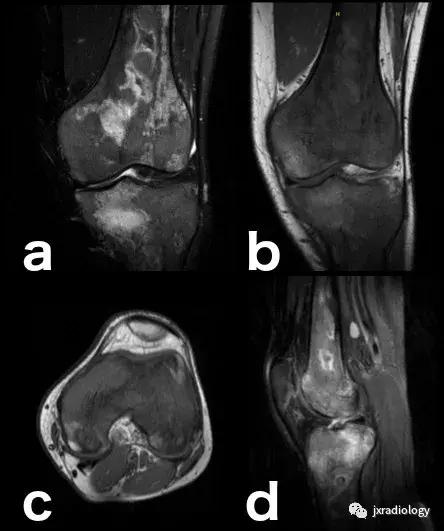

图20:患有血红蛋白病的患者(例如镰状细胞性贫血),在这种情况下,容易发生继发于毛细血管阻塞的骨坏死。这种阻塞导致毛细血管静水压升高,造成水敏性序列中低信号骨梗死周围的高信号水肿。这是充血性骨髓水肿的一个例子(由于骨髓空间毛细血管床液体流出受损)。该患者还表现出广泛的红骨髓转化,如T1-WI中的骨髓信号所示(远低于周围脂肪组织并略高于肌肉组织)和DP-FS-WI(未完全饱和,保持略高信号)( a:冠状面DP-FS-WI; b:冠状面T1-WI; c:轴向T1-WI; d:矢状面DP-FS-WI)。